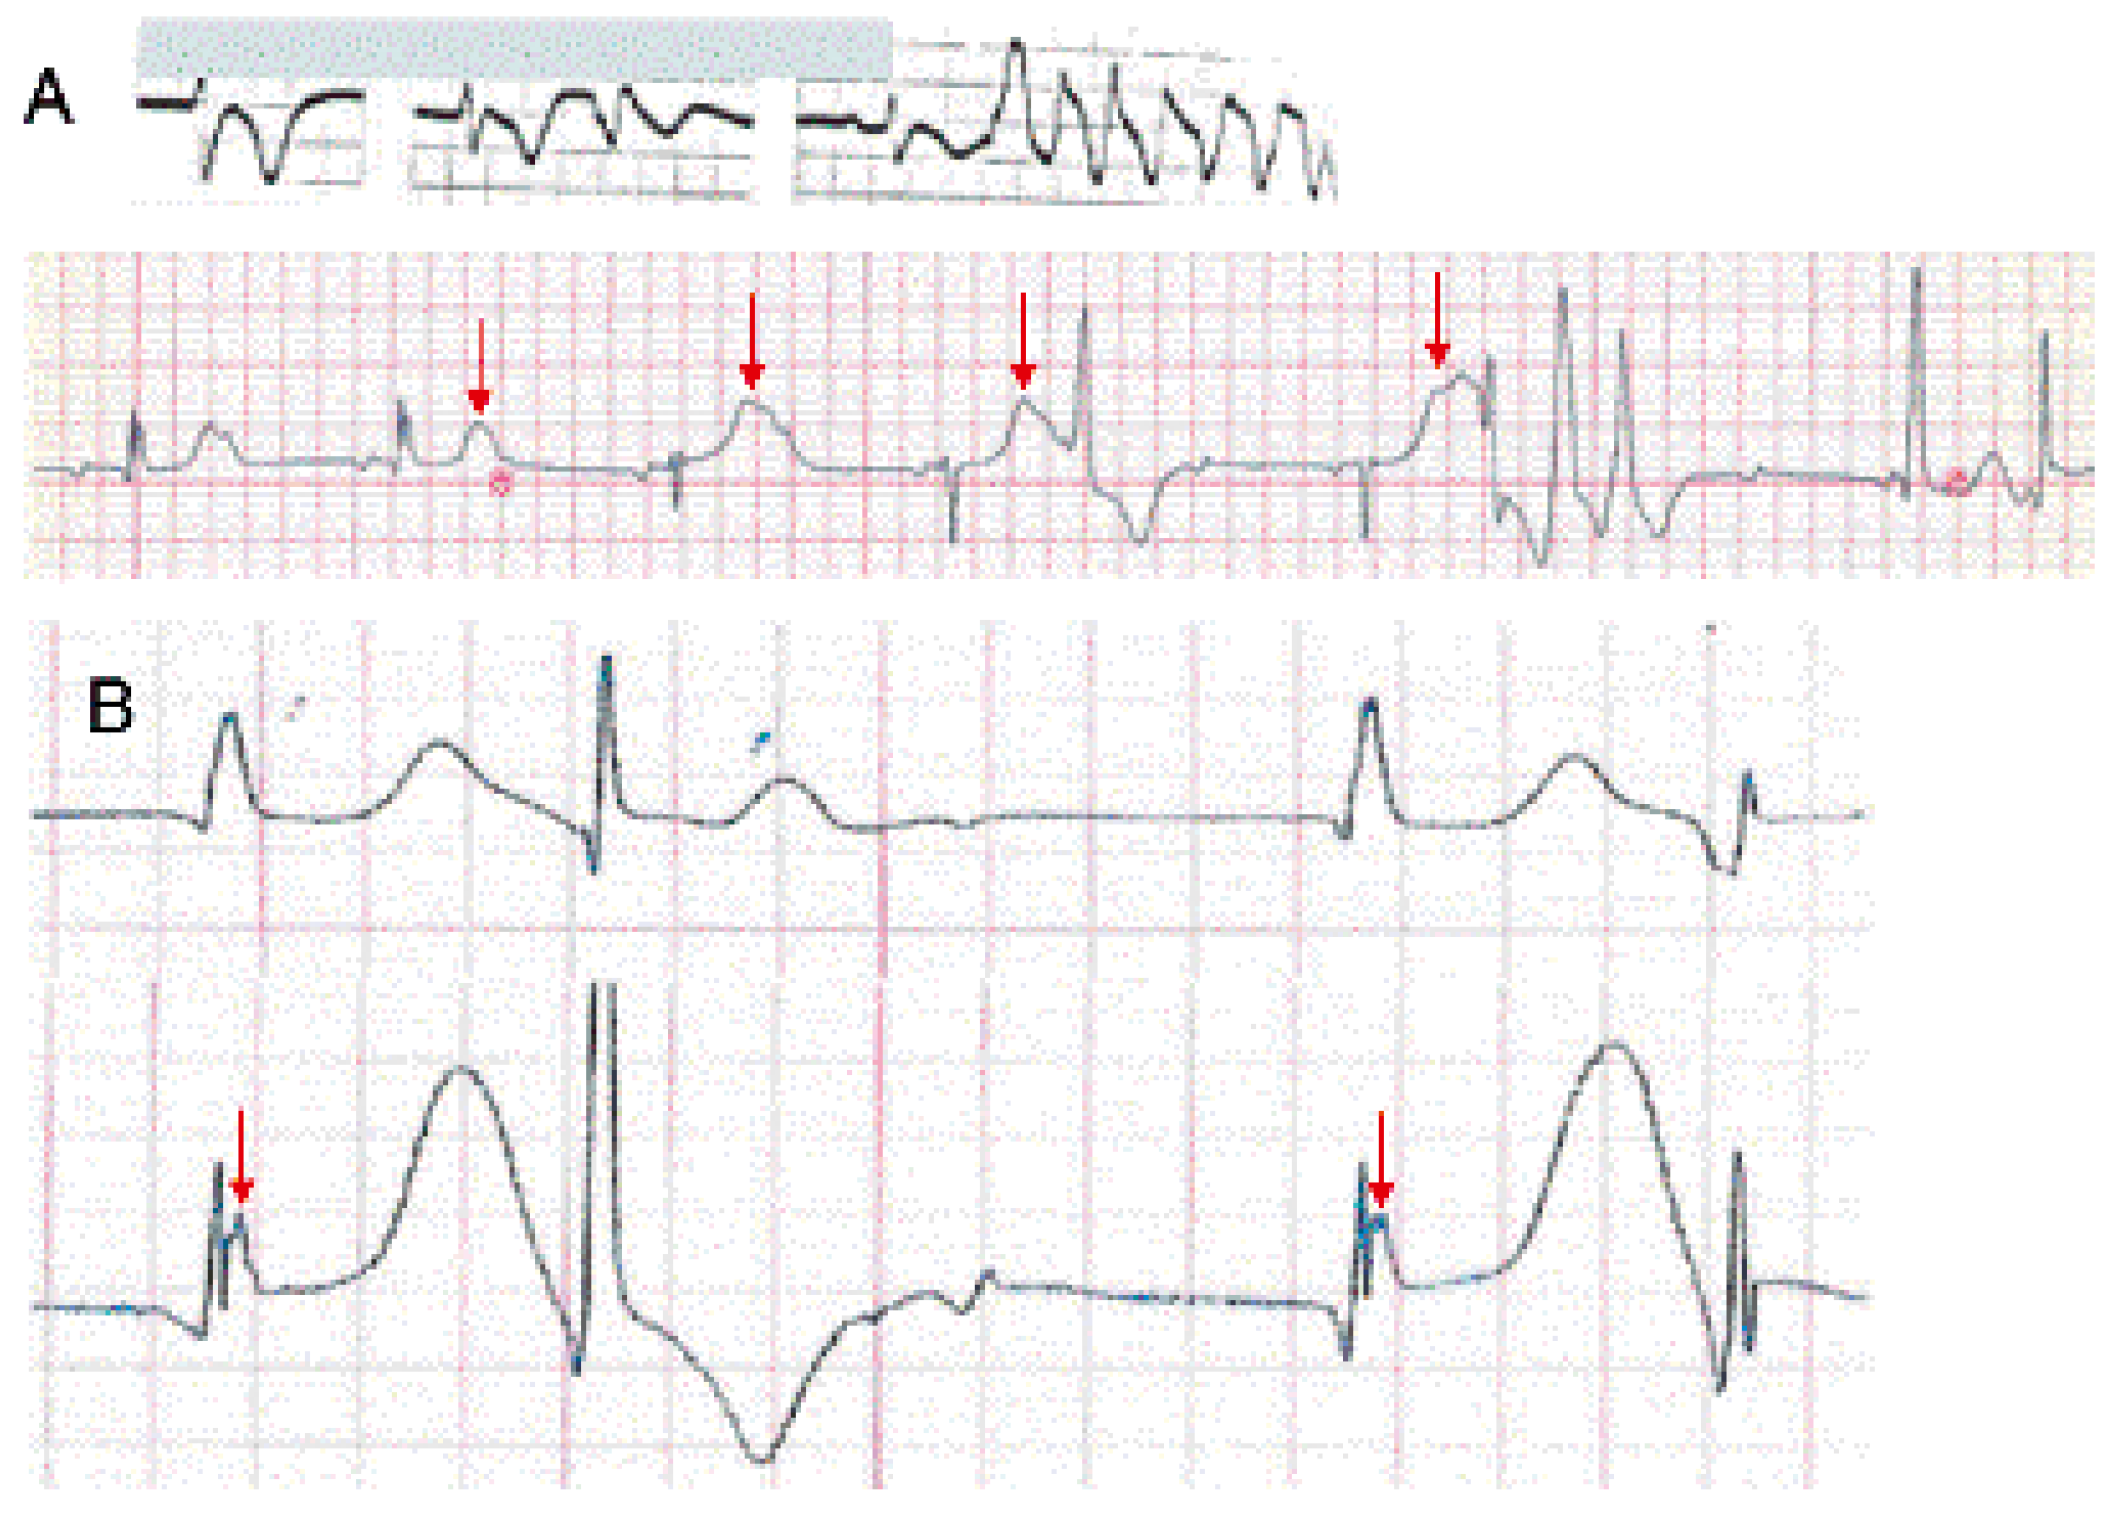

O25—A potential mechanism of Torsades de Pointes tachycardia in atrioventricular block

Background: Two mechanisms may explain the occurrence of Torsades de Pointes tachycardia (TdP) in atrioventricular block (AVB): (1) a phase 2 reentry phenomenon in adjacent myocardial fibers due to bradycardia and (2) a fast reentry circus movement. Therefore, the objective of this study was to investigate mechanisms of TdP, and to present for the first-time endocardial recordings during TdP from patients with high-degree AVB.

Methods: TdP was recorded by surface ECG in 16 patients with high-degree AVB. The critical coupling interval (CCI) between the last beat during AVB and before the first abnormal ventricular event (PVCs, couplets, triplets and TdPs) was measured. Endocardial signals during TdP were recorded from the right ventricular apex by temporary bipolar catheters.

Results: Patients were >65 years; 80% were females. The QT interval during AVB (mean heart rate of 38.9 ± 7.5 bpm) was 653 ± 67.2 ms. The CCI before the onset of PVCs/couplets vs. TdP was shorter in the latter (672 ± 43.8 ms and 676 ± 37 ms vs. 639 ± 52 ms, p <0.05). A rhythmic crescendo (in 100%) of PVCs and T wave augmentation (in 75%) was observed before the onset of TdP (figure, A, arrow). In 4/5 patients (75%) the local endocardial electrogram showed a constant pattern of rapid deflection superimposed on a smooth low amplitude signal suggesting far field potentials from electrically depressed myocardium, indicating a phase 2 reentry (figure, B, arrow).

Conclusions: This study suggests abnormal repolarization of adjacent ventricular myocardial fibers indicating a phase 2 reentry and fast reentry circus movement as the cause of TdP in patients with high degree AVB.

![]() |

| Figure |